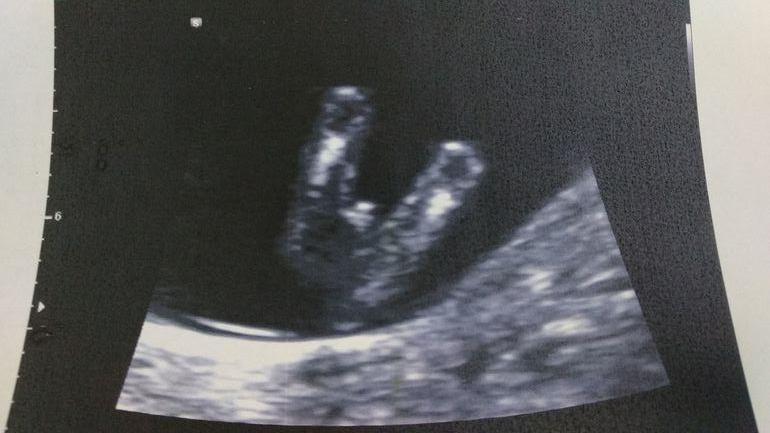

12 недель пол)

У вас не тот ракурс, чтобы можно было предположить.

Ну у вас тут хорошо видно что мальчик)

Мне тоже в 12 недель сказали мальчик)))) все верно оказалось.

Вряд ли кто-то скажет точнее узиста. В 14 недель уже определяют пол по размеру половых органов. В 12 недель по углу наклона. Мне в 12 недель две беременности определяли пол правильно. Тоже женский. Есть смысл поверить Вашему специалисту.

Девочка) Но это не точно 🥰